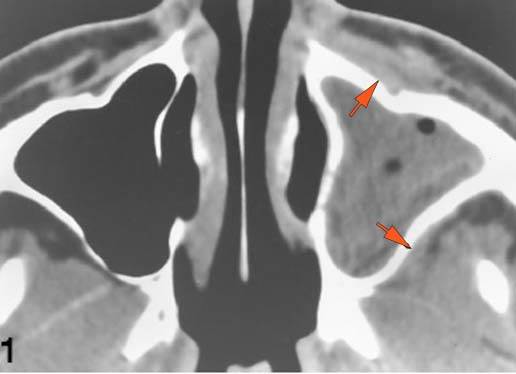

There is infiltration of the fat surrounding the nasolacrimal sac. [Yes/No]

There is infiltration of soft tissues or bone erosion along the nasolacrimal fossa or canal. [Yes/No]

The extraconal orbital fat is abnormal. [Yes/No]

There is a subperiosteal abscess or edema along the medial wall, roof or floor of the orbit. [Yes/No]